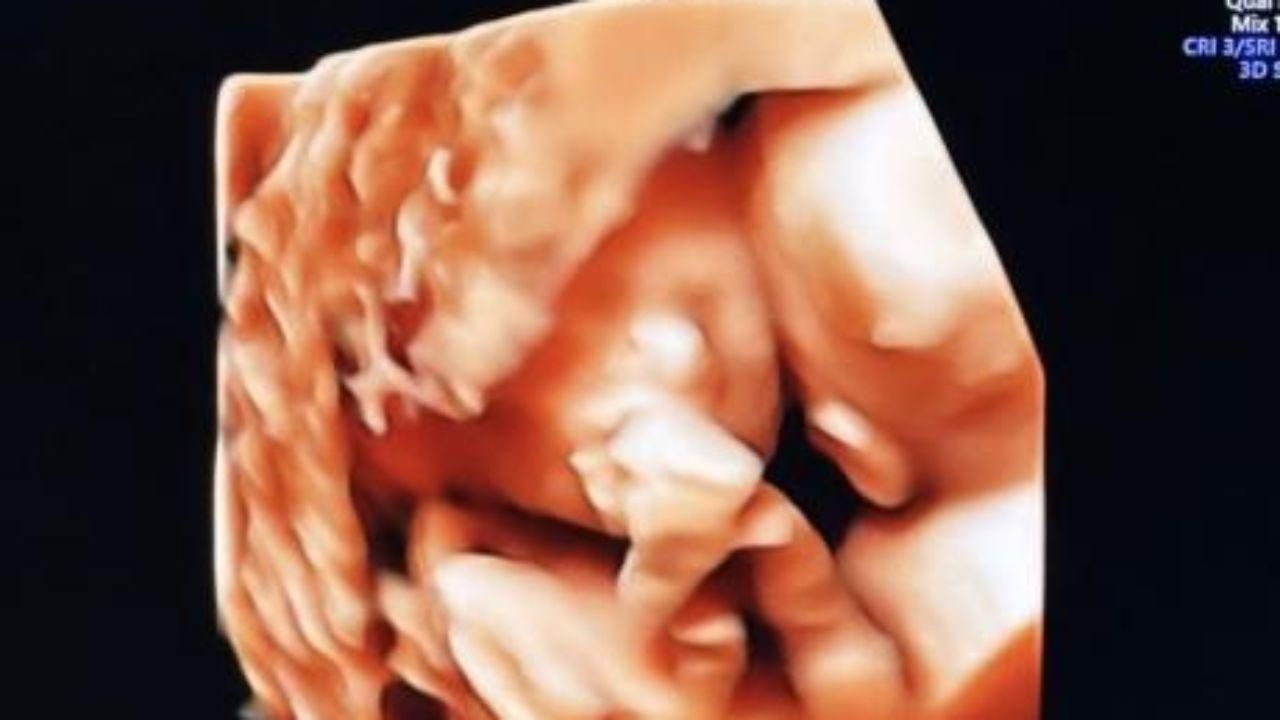

Il ballerino mostra l'ecografia delle gemelline che aspetta con Veronica Peparini: "Quella girata è la ricevente e quella di fronte è la donatrice"

Andreas Muller mostra sui social l'ecografia delle due gemelline che aspetta con Veronica Peparini. "Che meraviglia! Quella girata è la ricevente e quella di fronte è la donatrice. Fa quasi commuovere": il ballerino presenta così le bambine, riferendosi al problema che è stato riscontrato a Veronica Peparini durante un controllo.

"Comunque sta tenendo duro la più generosa, quindi il carattere già ci piace", aggiunge Andreas Muller, che poi pubblicando un'altra ecografia scrive: "La bellezza".